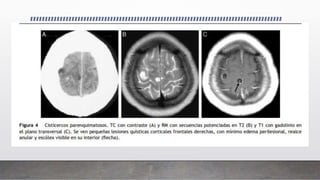

Cisticercos parenquimatosos

• La afección parenquimatosa es la segunda en frecuencia tras la aracnoidea.

• Los quistes se localizan preferentemente en la corteza cerebral y en los ganglios

basales donde hay mayor irrigación vascular. Estos quistes son generalmente

pequeños y raramente miden más de 10 mm de diámetro, ya que la presión que

ejerce el parénquima cerebral impide su crecimiento. Las formas

parenquimatosas incluyen diferentes fases evolutivas que van desde quistes

viables (quistes con escólex) hasta sus fases evolutivas finales con calcificaciones.

El uso de medio de contraste identifica lesiones con realce nodular en

los estadios no quístico y granulomatoso, y un realce anular de la

pared del quiste en el estadio vesicular-coloidal.

La obtención de las secuencias T1 en fases tardías tras la

administración de contraste incrementa la sensibilidad en la

detección de lesiones.